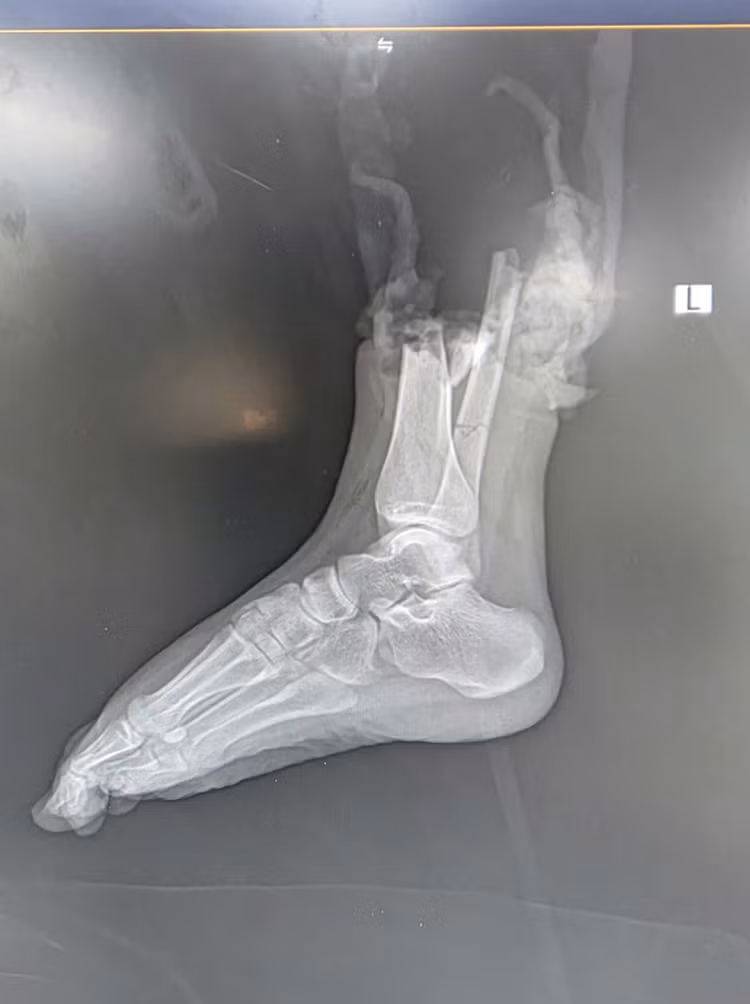

trong.jpg

Hình ảnh tổn thương trên CT - Ảnh BVCC